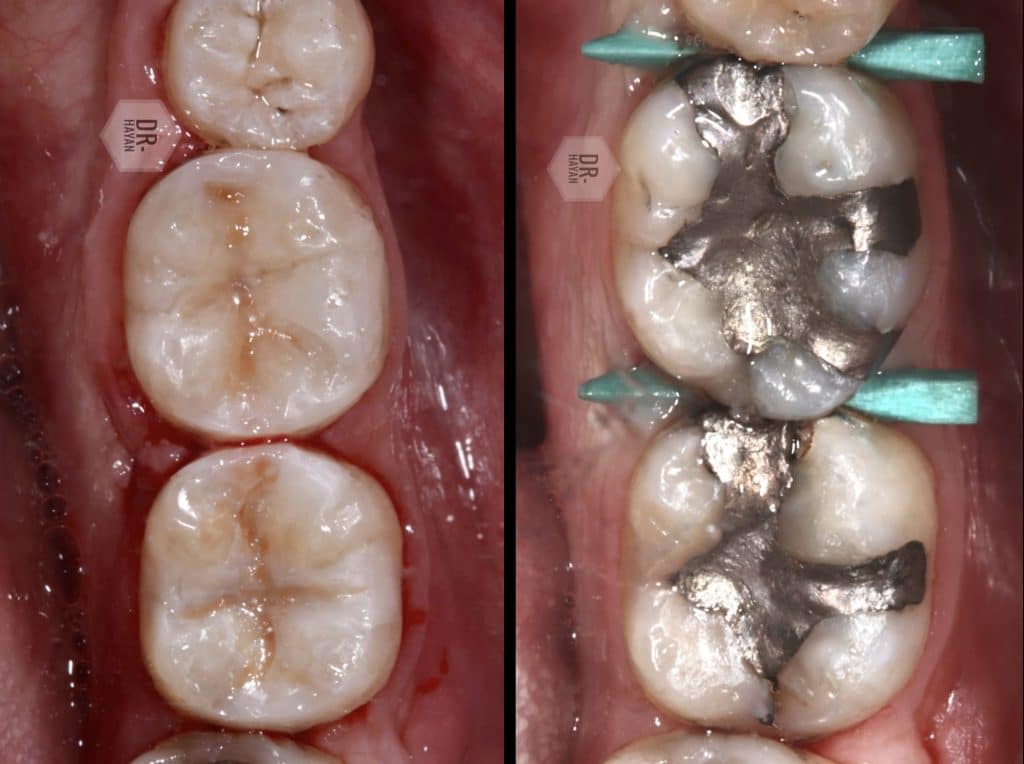

Before finishing and polishing

After 1,30 hours of fighting

Finally, after finishing and polishing protocol